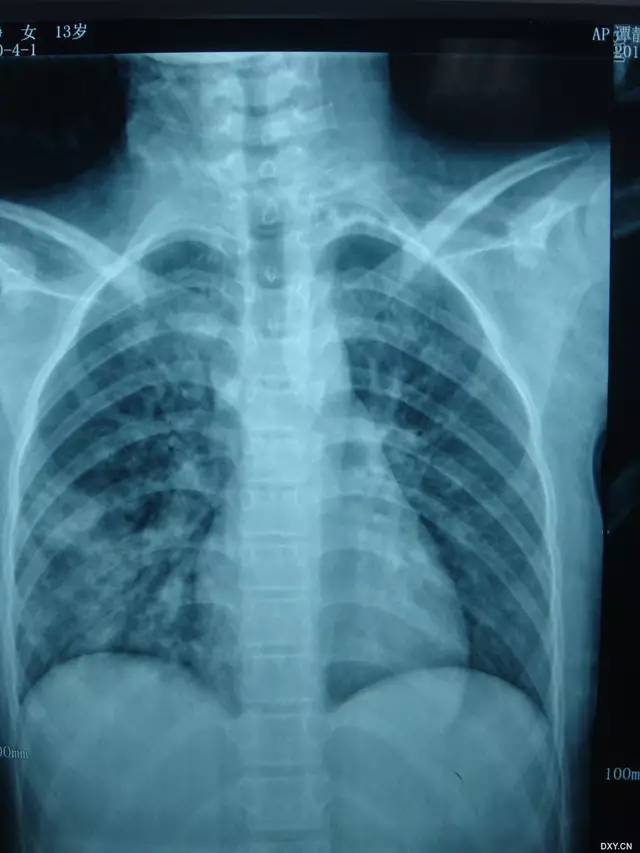

病例六(来自丁香园战友 xbfiuy 发布)

基本病史:女、13 岁,因反复咯血 8 年、再发加重 10 天入院。多次在医院治疗(止血抗炎、支气管动脉栓塞等),症状反复。10 天前再次发作并呼吸困难。既往有百日咳病史,行胸部影像学检查结果如下:

图 7 胸部 X 线显示双肺弥漫性高密度影,以右肺下叶为著